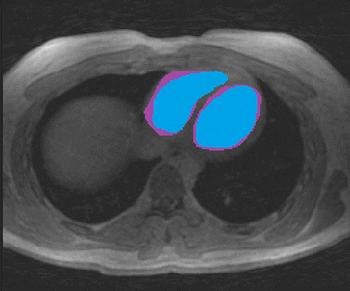

New study, comparing recovered athletes to healthy controls, reveals a lower level of myocarditis that previously published research, but cardiac MRI is still important for safe return-to-play decisions.

Scans identify evidence of the condition in 15 percent of athletes who have rebounded from viral infection.

Performance of 0.55T MRI is comparable to 1.5T MRI in acquiring and interpreting late gadolinium enhancement in patients suspected of myocardial infarction, research shows.

Scans show cardiovascular impact lingers after the acute phase of viral infection and into recovery.